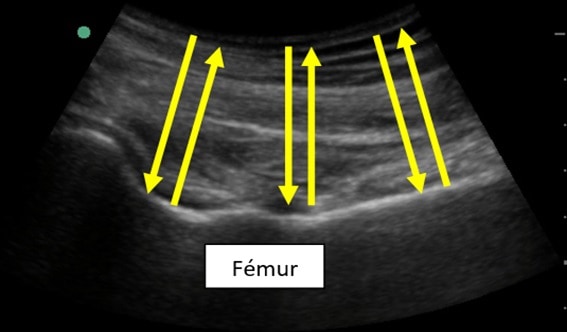

En la imagen siguiente, se puede apreciar el fémur de un paciente. El ultrasonido llega hasta la interfase del hueso (muy denso) con el tejido circundante (muy poco denso) y se refleja con una intensidad alta (y por eso se muestra más “blanco” en la pantalla, como luego veremos).